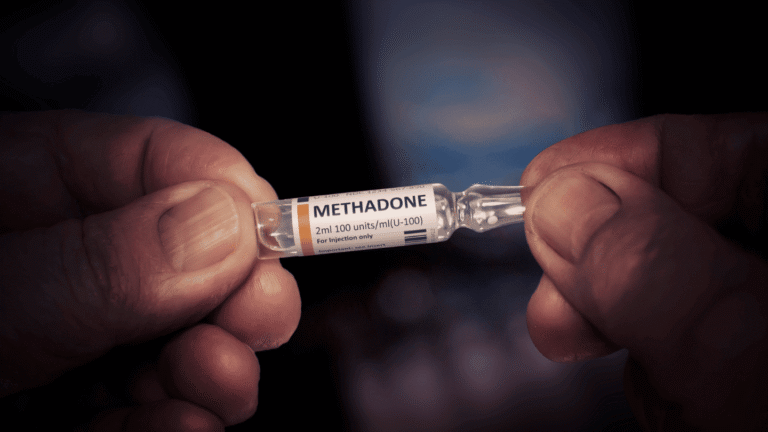

For those ready to break free of opioid dependence, buprenorphine and methadone…